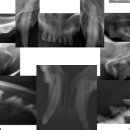

• 목동찬동물의료센터 | 내돈내산 | 고양이 구내염 치주염 치석에 좋은 고양이 치약, 칫솔 추천!

약 먹이는 것 처음 해봤는데 .. 저 생각보다 잘 먹이는 것 가타욤 ㅎㅎ .. (걱정했는데 .. 야호 돈 굳었당 헷 ..) ​ 한 번에 쑈옥- ✌️😘 ​ 병원은 요기!! ​ 목동찬동물의료센터 서울특별시 양천구 오목로 285 1층 그래서 바아로!! ​ 가장~ 유명하고~ ​ 이미 별밭이 형님인 레오 형님이 사용하고 있는 오라틴 메인터넌스 투...

느리지만 행복하게 ෆ(2025-10-31 22:45:00)